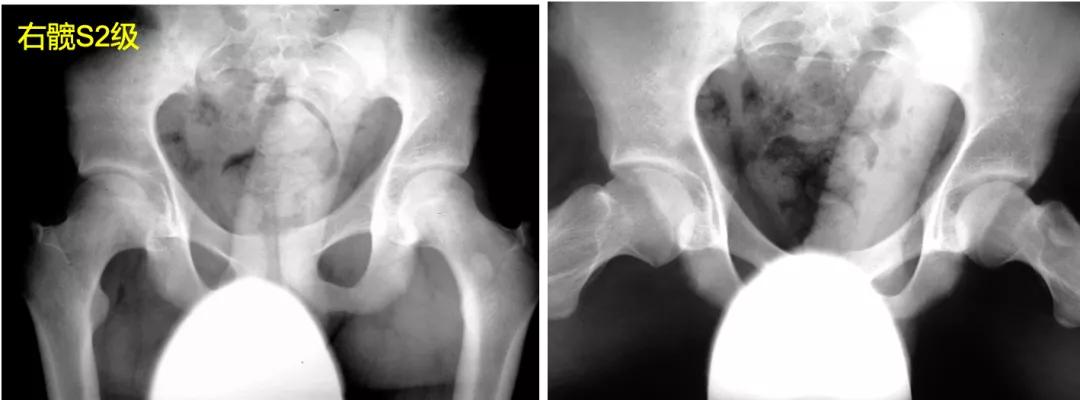

S1:影像学正常髋关节。

S2:股骨头呈圆形(不圆不超过2mm),在髋关节正侧位片中与髋臼呈同心状,但存在股骨头膨大、股骨颈变短。